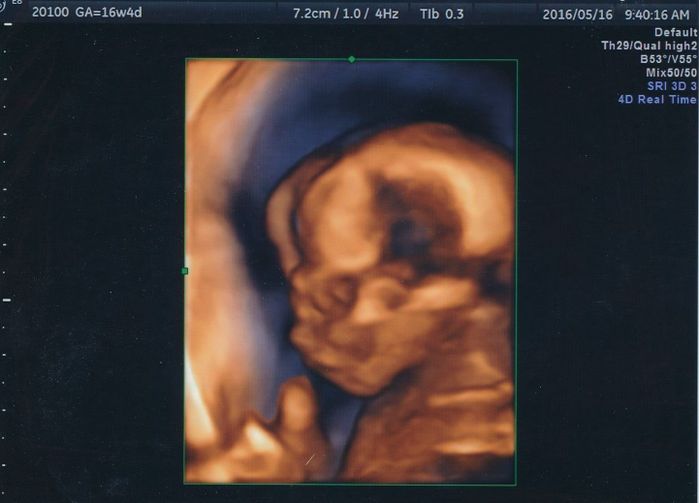

妊娠16週目のエコー写真

赤ちゃんの顔が正面からはっきり写っています。目鼻立ちも分かるので、赤ちゃんの顔を想像していたように思います。あごの近くにある2つの白丸は小さな両手です。

こちらは4Dです。赤ちゃんが指しゃぶりをしているところが撮れました。実際には口がパクパクと動いていたように記憶しています。